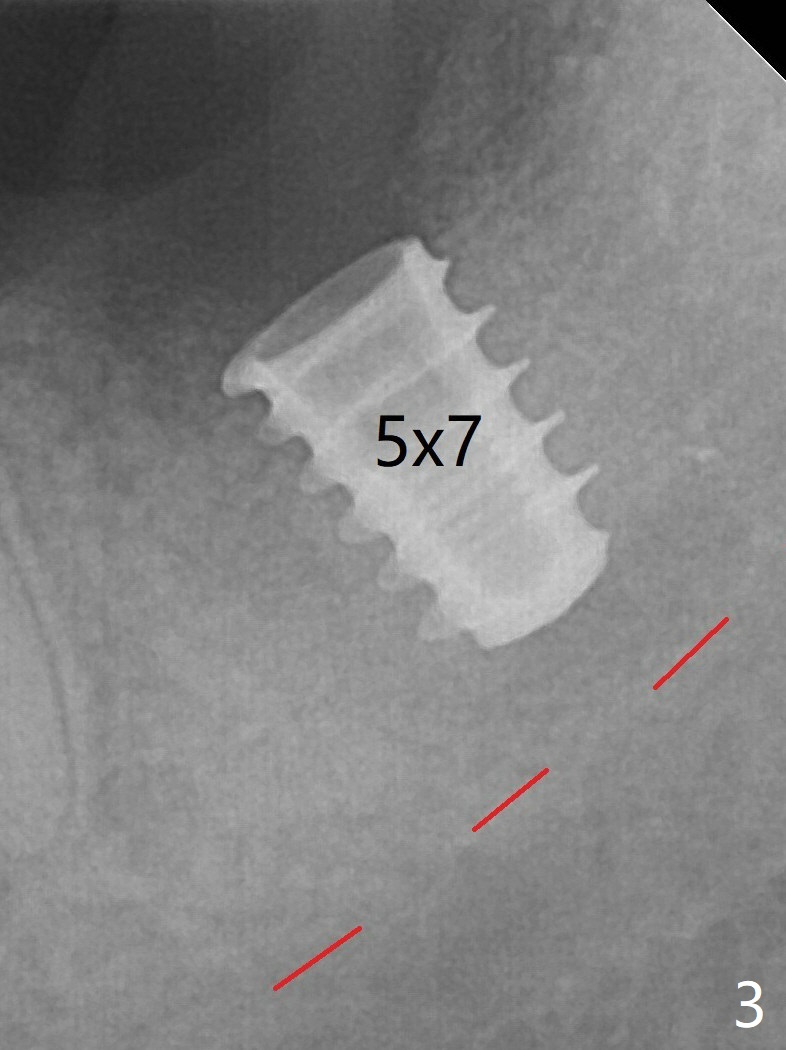

Since a 5x7 mm IBS implant is placed incompletely (Fig.3), a 4.3 mm MD is used for ~1 mm deeper. The implant is reseated to more satisfactory level (Fig.4: ~ 1 mm from the upper border of the Inferior Alveolar Canal (red dashed line)). Impression is taken 5 months postop (Fig.5,6).